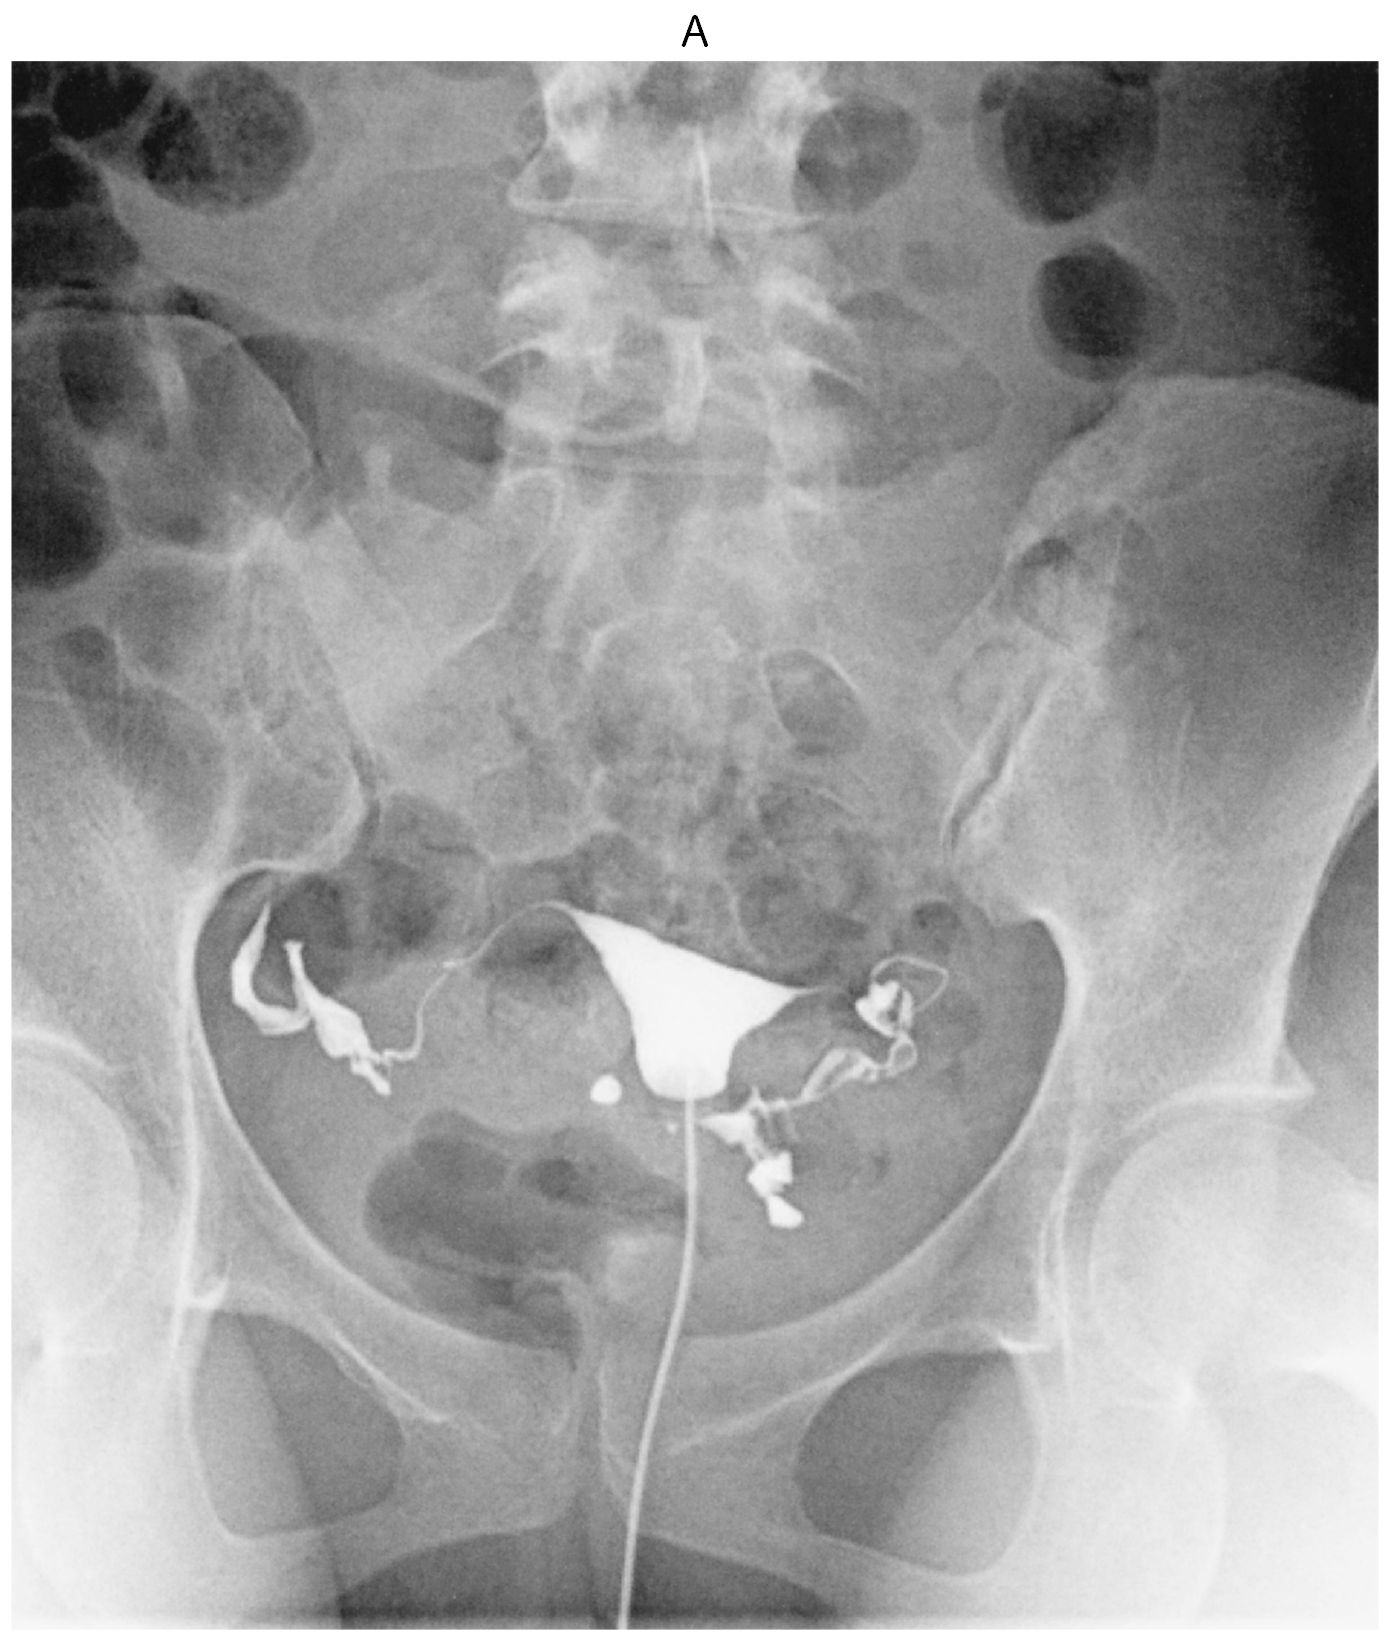

35歳の女性(0妊0産)。挙児を希望して来院した。1年前に結婚してから避妊はしておらず,1か月に1回程度の性交があり,軽度の性交痛がある。初経12歳。月経周期は30~40日型,整,持続6日間。月経痛は認めない。基礎体温は2相性である。身長162cm,体重55kg。内診で子宮は正常大で,両側付属器は触知しない。血液生化学所見(月経3日目):LH 5.2mIU/mL(基準1.8~7.6),FSH 8.2mIU/mL(基準5.2~14.4),プロラクチン〈PRL〉8.6ng/mL(基準15以下),エストラジオール42pg/mL(基準25~75),テストステロン60ng/dL(基準30~90)。夫の精液検査は正常である。子宮卵管造影像(A)(B)を下に示す。